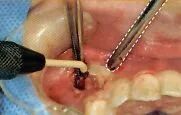

8 去除和刮治不良肉芽组织

拔牙窝最深处需要医生探头去看。所以口腔卫生士尽量要抓住医生不处于探头看的时候进行吸唾操作。有部分医生也可以独自完成治疗和吸唾的操作。

存在重度牙周病的牙齿,在其牙颈部和根尖部长有不良肉芽组织。这些不良肉芽组织会成为术后出血的诱因,因此要事先用刮匙将其彻底清除干净。

吸唾器的操作目的

1,确认拔牙窝处是否残留了部分破损的牙冠、牙根以及碎屑。

2,确认邻牙上是否附着牙结石,是否有龋蚀。

3,刮治过程中,保证不良肉芽组织周围术野。

吸引拔牙窝。不过,拔智齿时,可能会暴露下牙槽神经。向医生确认下牙槽管是否有暴露的可能性之后,再吸引拔牙窝底部。对口腔卫生士而言必须依靠经验掌握插入吸唾器的深度。

此外,进行刮治时使用吸唾器吸引刮匙操作的区域。

刮治后,为了确认邻牙是否有牙结石附着和龋,可以使用吸唾器吸引邻在牙侧面。医生和其助手的术野是不同的。特别是较小拔牙窝,根据角度的不同,可能会导致主治医生观察时视线被阻碍。口腔卫生士在确认了是否有不良肉芽组织残留和破损牙根之后,要将自己所处角度看到的情况传达给医生。

刮治时吸引手刮匙的操作部位